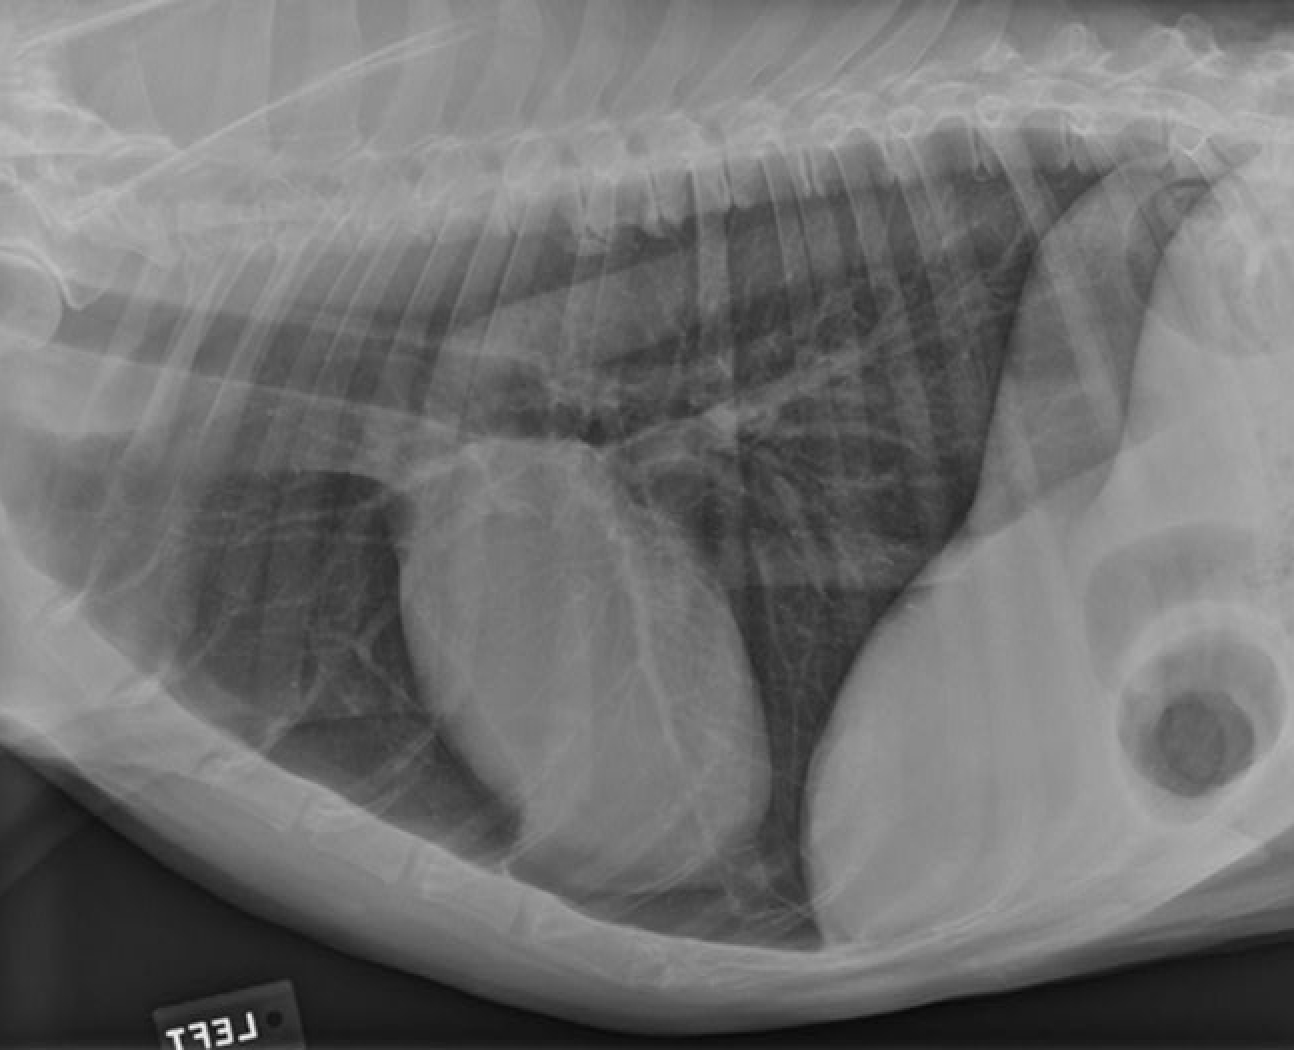

identify the structures of the cat thorax

A= heart

B= diaphragm

C= liver

how does the shape of the cat thorax differ than the dogs

shape: narrow and steep, heart sits more at an angle and it is positioned more caudally (4th-7th intercostal space) also little of the heart is covered by the forelimb as the triceps reaches no further than the 4th rib

Identify Manubrium of sternum, First rib, Apex of heart, Base of heart, Diaphragm and First lumbar vertebra

Again note the shape of thoracic cavity. How does it compare to that of the dog?

Narrower particularly about the thoracic inlet